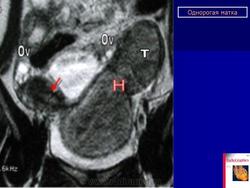

МПС. Женская репродуктивная система. Аномалии и варианты развития. Матка. Однорогая матка. +

Аномалии и варианты развития. Однорогая матка.